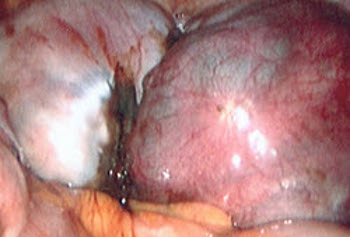

Endometriose: imagem laparoscópica de endometrioma ovariano

Do acervo de Dr. Jonathon Solnik; usado com permissão